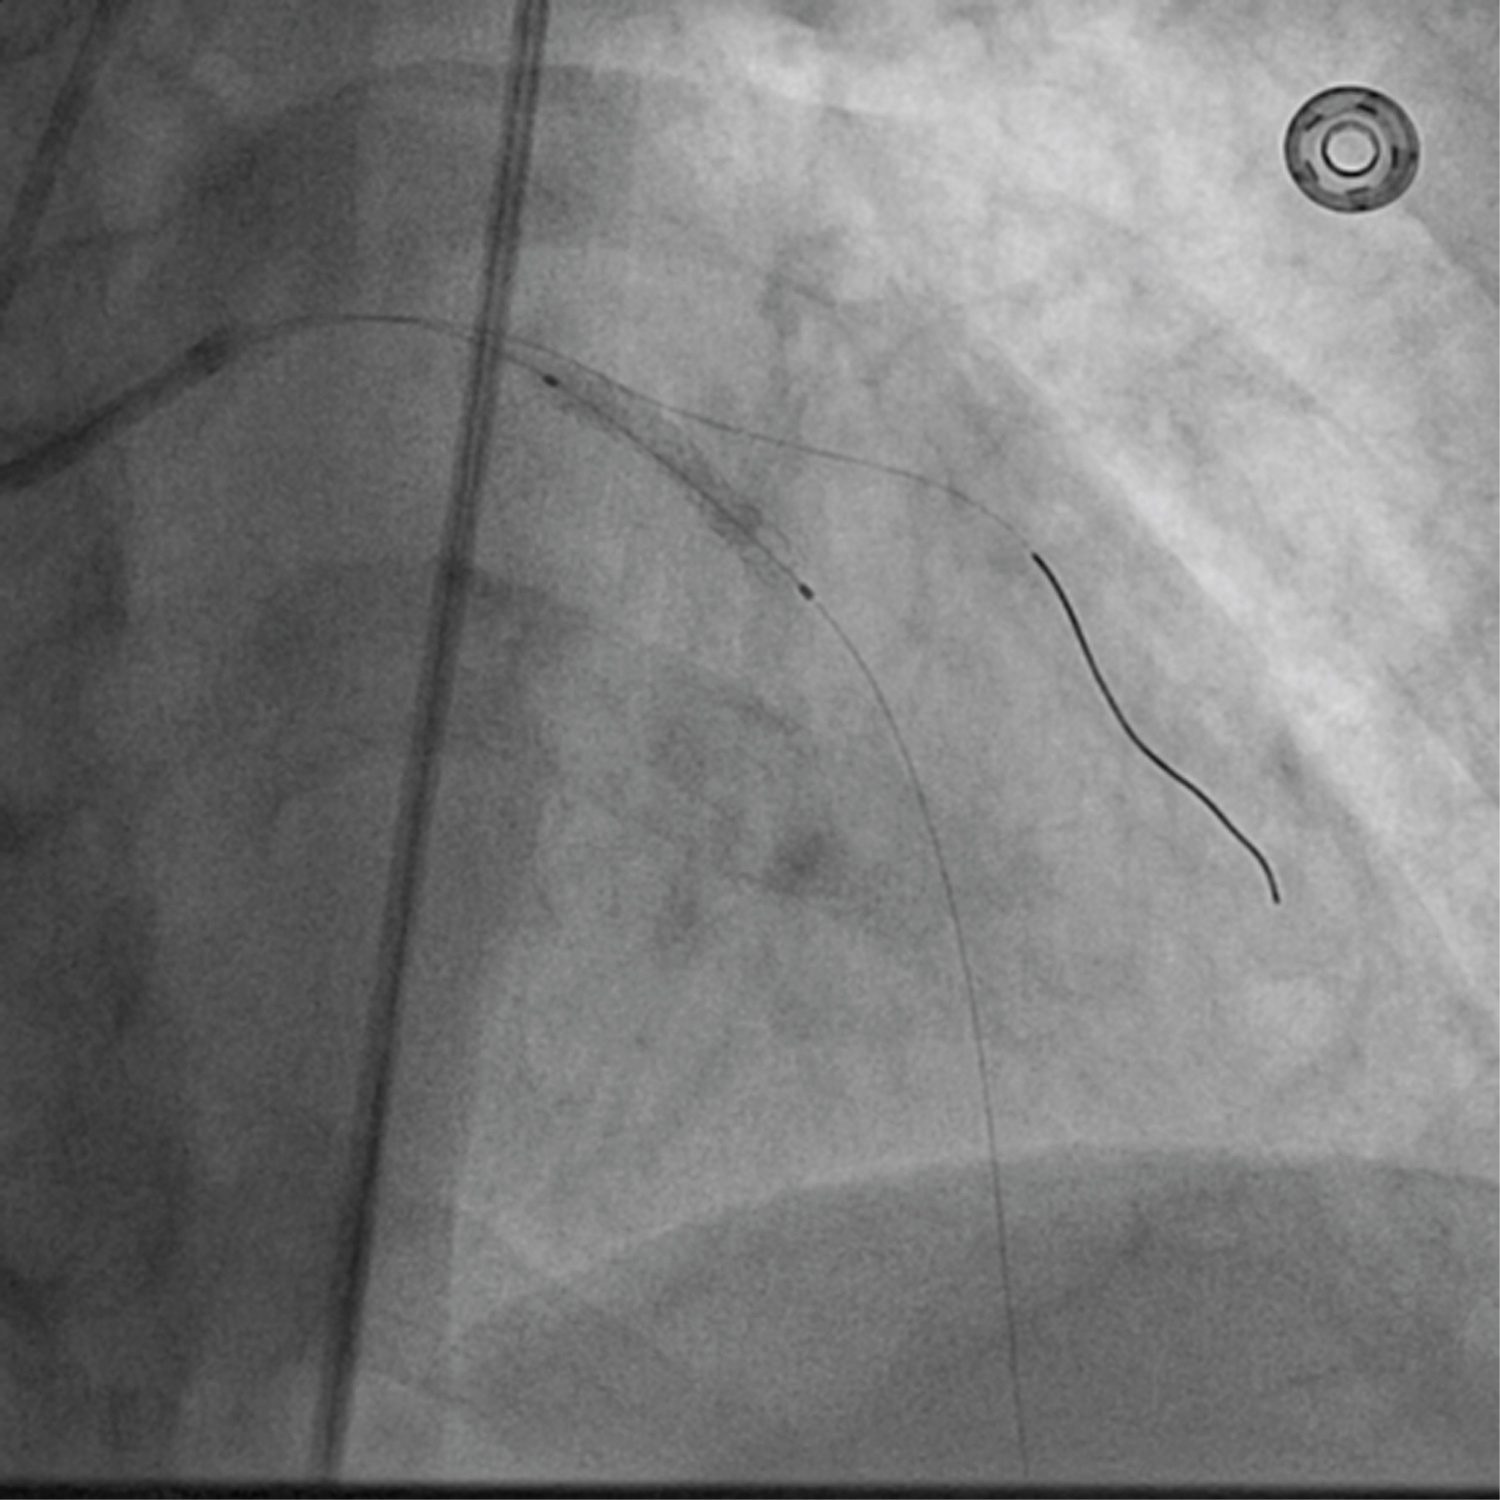

A 75-year-old diabetic and hypertensive male presented with chest heaviness with sweating of 6 hours duration. An electrocardiogram showed marked ST elevation in V1-V6. Routine haemogram and biochemistry was normal except deranged renal function with serum creatinine of 3.3 mg%. His body weight was 68 kg. Echocardiography revealed mild concentric left ventricular hypertrophy, regional wall motion defect in left anterior descending territory (LAD), and impaired systolic function with an ejection fraction of 40%. His coronary angiogram was done through transfemoral approach after proper consent revealing critical lesion with 90% stenosis in mid left anterior descending (LAD) artery just after large diagonal branch, normal left circumflex territory, and right coronary artery (Figure 1 and Figure 2). The coronary angiogram was completed using 9 ml of contrast. The contrast used was iodixanol which is an iso-osmolar contrast agent. Primary PCI was planned subsequently. Intravenous heparin (100 U/Kg) was administered. Based on all the baseline factors, it was a high risk PCI carrying a profound risk of CIN. To minimize the risk of CIN, intravenous normal saline infusion was started. Prior to PCI, initial angiogram with same angle of projection was uploaded to the monitor for PCI guidance. Left main artery was engaged with 6F extra backup guiding catheter (EBU; Medtronic, USA) which was confirmed by entry of the runthrough wire (Terumo, Japan) into the coronary artery. An exaggerated curve was created to facilitate the wiring of LAD. Additional runthrough wire was placed in first diagonal branch (D1) based on the previous angiogram (Figure 3). The side branch wire served as an important landmark to guide PCI and to protect the side branches as well. The balloon was positioned just after D1 which was used as a landmark for proximal end for stent placement. Lesion was gradually predilated with 2 × 10 and 2.5 × 10 pantera leo semi compliant balloons (Biotronik, Germany). 3 × 23 mm Endeavour Resolute (Zotarolimus eluting stent; Medtronic, USA) stent was positioned across the lesion keeping the proximal end at the crossing of LAD and D1 wire which was serving as the origin of D1 (Figure 3). It was deployed at 13 atm pressure (Figure 4). As it was not fully expanded, it was serially post dilated by 3 × 10 and 3.5 × 10 non-compliant Minitrak balloon (Abott, USA) at 24 atm pressure. The stent apposition was checked under stent boost. After confirmation of stent optimization with stent boost, final angiography with 4 ml contrast injection revealed successful results (Figure 5). Therefore, PCI was completed using 13 ml of contrast. He was clinically stable for 2 days without CIN (Serum creatinine 3.5 mg/dL). She was discharged 2 days after PCI with appropriate drugs and has been uneventful.

Figure 4: Stent was deployed at 13 atm pressure. View Figure 4